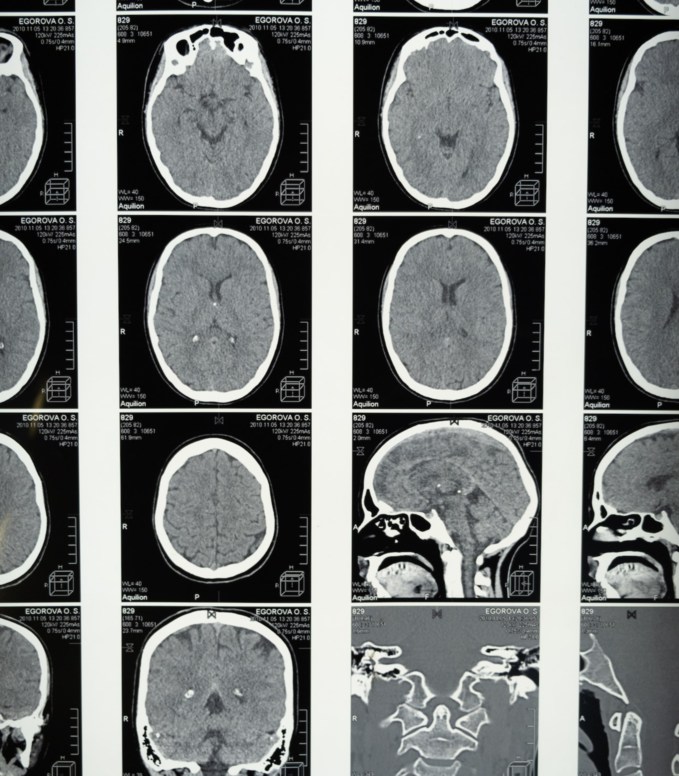

The significance of accurate MRI report translation cannot be overstated when it comes to ensuring patients’ proper diagnosis and treatment. A single erroneous translation could lead to a chain reaction of misdiagnoses, misguided treatment plans, and subsequent complications to a patient’s health.

Medical professionals universally emphasize the importance of verifying and ascertaining that any MRI report used in patient care contains original information that has been faithfully translated. This thoroughness is critical to guarantee that patients receive the correct and effective treatment.

Moreover, the significance of accurate MRI reports becomes profoundly pronounced in avoiding unnecessary medical tests and procedures. In critical medical conditions, swift and precise diagnosis can be the difference between life and death.

When MRI results are verifiable and error-free, medical professionals can make prompt and well-informed decisions, removing redundant tests and procedures that might exacerbate a patient’s condition. This optimizes healthcare efficiency and resource allocation and minimizes the physical and emotional strain on patients, who can rest assured that their treatment plans are optimized for their specific needs.